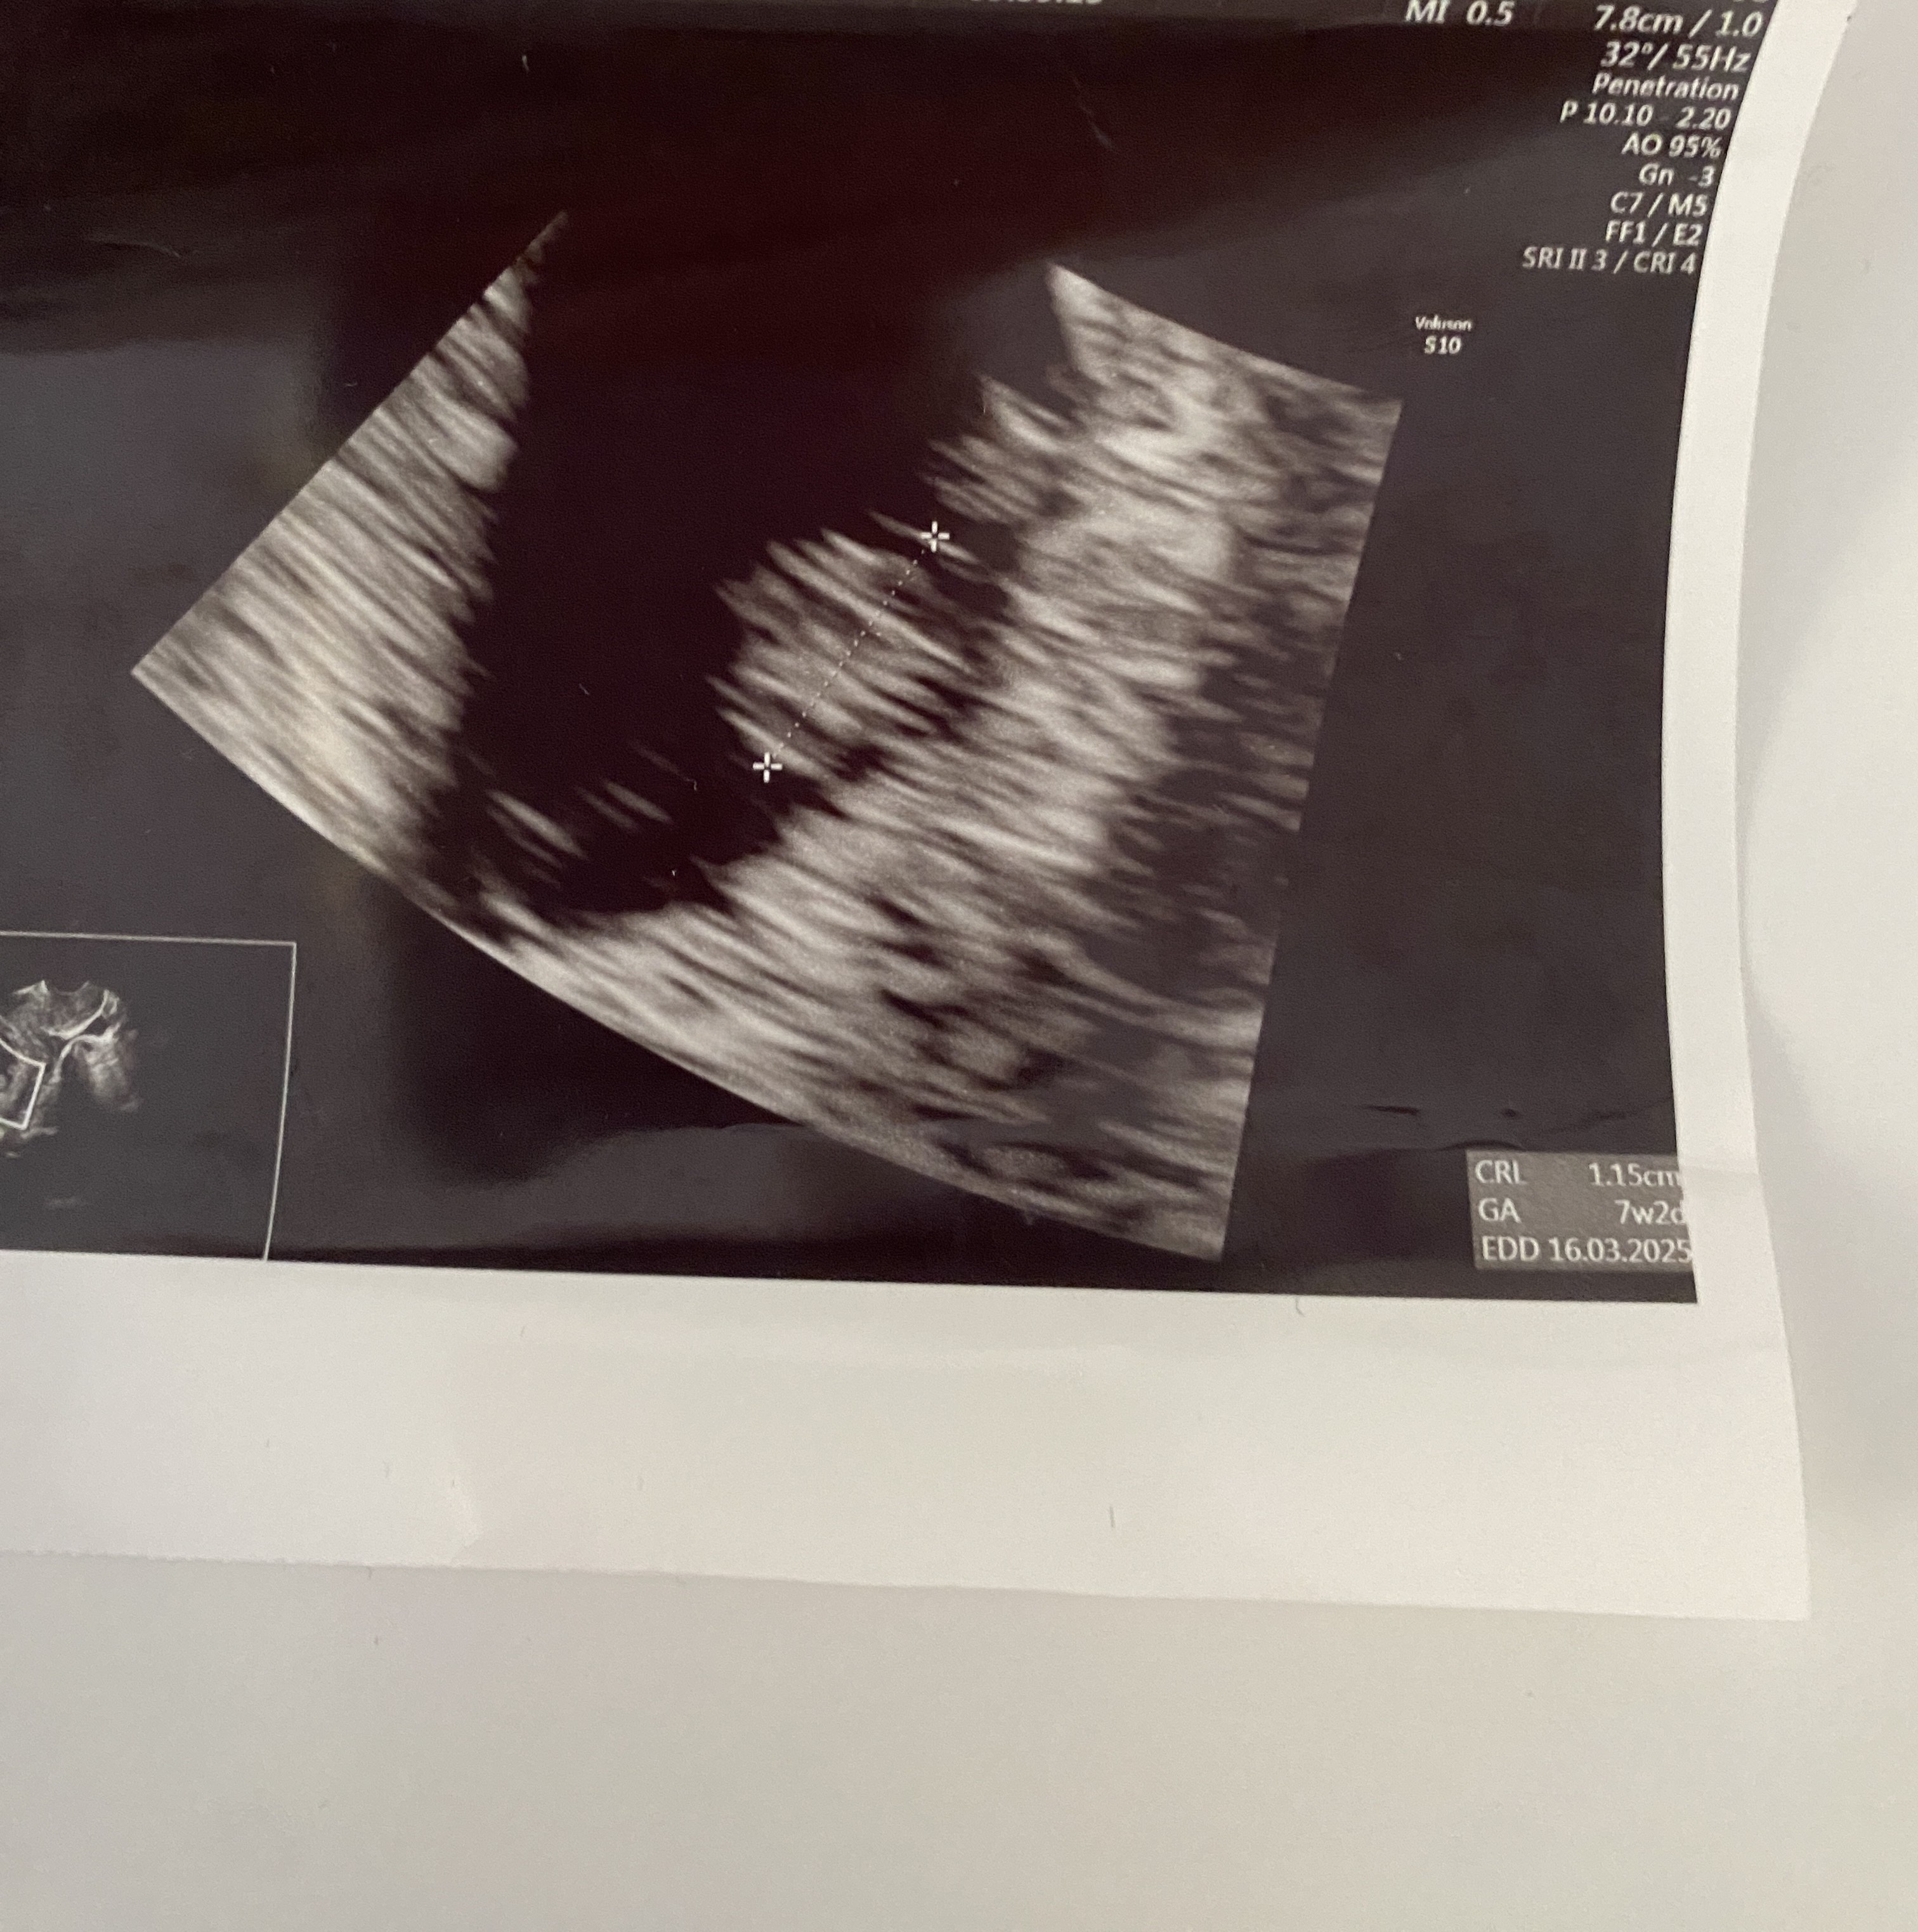

Hej , ost miesiączka 6 czerwca , jestem w ciąży dwa tygodnie temu według usg ciąża mi wychodziła starsza i termin na usg to 5 marca i 6+6 a po dwóch tygodniach na wizycie termin na USG pokazuje 16.03 i 7+2 ale serduszko bije . Zaznaczę Że poprzednią ciążę poronilam w 8 tyg a tera też mam brązowe plamienia . Lekarz pow że na ten moment wszystko ok ale mi się nie wydaje …. Ktoś miał podobny przypadek ?

Ale 1 usg to zapewne pęcherzyk a 2 to już zmierzony zarodek wieć nie ma co tych wartości porównywać. Moim zdaniem kiepsko to wygląda,że przez 2 tygodnie ciąża ma ten sam wiek. Nie mniej jednak wiek pokrywa się z ostatnim dniem miesiączki, więc może rzeczywiście ten pierwszy pomiar i wyliczenia są błędne.